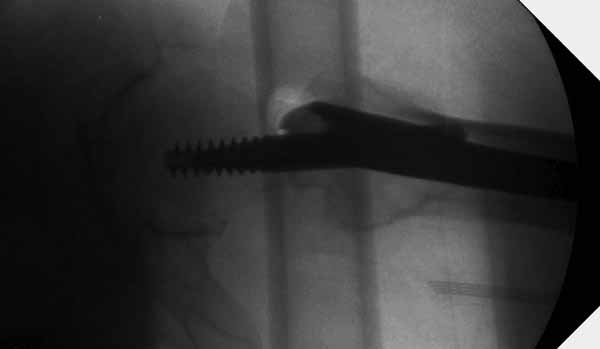

Банальный рутинный перелом чрезвертельной зоны лечимый DHS.

А по картинке можно сказать, что вроде бы все и неплохо. Предупредить миграцию шеечного винта при наружной ротации диафиза во время ходьбы достигают введением последнего поближе к переднему кортексу шейки. На Вашей картинке винт "смотрит" кзади. Отсутствие дополнительной боковой опоры для винта создает предпосылки для несостоятельности фиксации. (См. статью в прикреплении). Поэтому с ранней активизацией пациента в данном случае я бы подождал.

А пациент-то какой из себя?

При таком переломе мы бы тоже поставили вертельный гвоздь - на следующий день встать и побежать - чем не перспектива? На прямом снимке винт стоит замечательно, а коварный аксиальный подкачал, хотелось бы больше по центру шейки и головки завести. Да и смещение, какое-никакое, но есть. Посему - нагрузка 15 кг, а расширяли бы не раньше, чем через 5 недель.

Что касается данного перелома, то по-моему DHS или гамма - принципиальной разницы здесь конкретно нет - медиальная опора сохранена, при правильном исполнении можно ногу нагружать. Технически здесь выполнено на 3+, но если так же винт гаммы поставить - лучше не было бы.

Прилагаю снимок сделанный еще в стационаре через 2 недели после операции.

Первые снимки показывают технические погрешности установки DHS. Не была достигнута репозиция, конечность в флексии и шейка в ротации. Сегодня все меньше обращают внимание на параметры для оценки репозиции (S контуры Lowell в обеих проекциях и Garden Alignment Index, в норме 155 и 180 градусов), хотя такие простые тесты помогли бы дорепонировать смещение. Винт находится сзади в головке, что при нагрузке поменяет вектор и вместо компрессии в линии перелома срежет головку-Cut Out!

В зависимости от дистанции линии перелома и латерального кортекса надо использовать разной длины barrel, т.е. конец баррели не должен доходить до пределов перелома. Здесь конец длинного ствола упирается в медиальный фрагмент, что мешает созданию компрессии, а более короткий barrel создал бы запас для компрессии. В боковой пластине вместо 4х можно было ограничится двумя шурупами, потому что головка шурупа в 4.5 мм выдерживает давление до 350 кг.